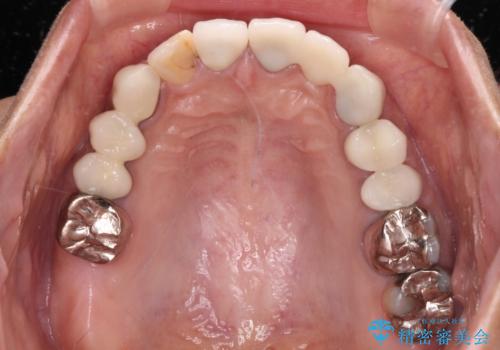

歯を削る量は増えますが、より長い期間再治療なく使用していただくことを最優先に考え、フルカバレッジのオールセラミックブリッジにて補綴することとしました。

他にも、奥歯の銀歯の下にもむし歯が多くあり、痛みが生じていたため、根管治療などを行った上で、オールセラミッククラウンにて補綴治療することとしました。

我々としては、治療により状態が悪化することだけは避けたいと考えているため、歯全体を覆うクラウンにすることで、より長持ちする治療を提供いたしました。

外観はもちろんのこと、隙間なく安心して咬むことのできる前歯となり、患者様には大変満足していただきました。